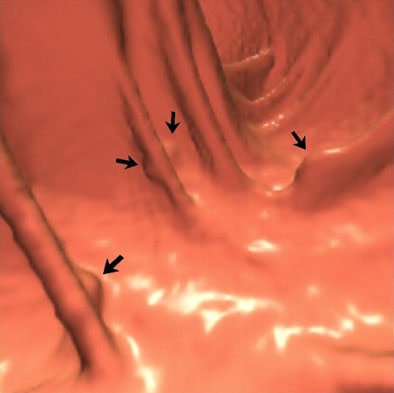

| A 64-year-old man was referred for initial colorectal screening. Endoluminal 3D (above and below) and coronal 2D (bottom) images from screening CT colonography showed multiple subcentimeter polypoid lesion (arrows). Images below and bottom show the same lesion on 3D and 2D, respectively. Lesions were all of soft-tissue attenuation and measured up to 9 mm. Images reprinted with permission of the American Roentgen Ray Society (ARRS) from Lee et al, AJR 2006; 186:1113-1115. |

"Multiple polypoid lesions measuring up to 9 mm and located within matching colonic segments were confirmed at optical colonoscopy performed several hours after CT colonography," Andrews et al wrote. "The lesions, however, were not mucosal polyps, but instead were well-defined raised submucosal vascular blebs with a distinctive bluish hue. Biopsy was not performed because of the vascular nature of the lesions, combined with the fact that the endoscopic appearance was characteristic and diagnostic."

"Vascular lesions, such as the venous malformations or vascular blebs shown in the current case, represent a rare submucosal cause of polypoid lesions on CT colonography and, to our knowledge, have not been reported previously," Lee et al wrote. "In general, mucosal versus submucosal origin of small focal lesions is sometimes a difficult distinction on CT colonography."